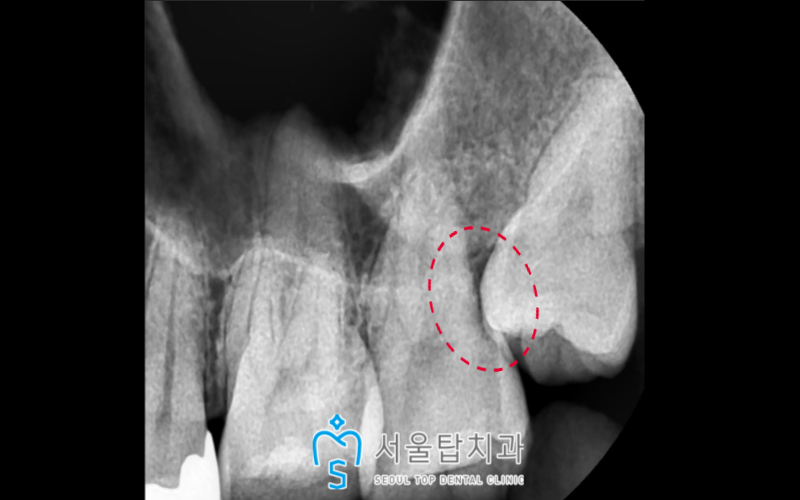

우식이 치근 쪽에 있다 보니

이 경우 치료를 통해

살려 쓰기는 어렵다고 판단이 되어,

왼쪽 위 두 번째 큰 어금니(#27)와

사랑니(#28) 모두 발치를 하고

두 번째 큰 어금니가 있던 자리에는

임플란트 식립을 진행하기로 하였습니다.